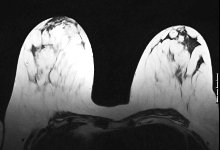

Профилактика рака груди проводится в Германии в основном между 50-м и 70-м годами жизни. Но значительное количество женщин заболевает раком груди еще до 50-летнего возраста, а еще большее количество – после 70 лет. Также в эти периоды жизни маммография и УЗИ грудной железы являются отличными методами в смысле профилактической диагностики рака на ранней бессимптомной стадии. По-другому выглядит ситуация у женщин, имеющих повышенную наследственную предрасположенность или находящихся в ситуации повышенного риска. У этих женщин магниторезонансная томография (МРТ) является обследованием груди, при котором с большой вероятностью обнаруживаются предстадии рака груди (DCIS). Магниторезонансная томография (ЯМР-томография) женской груди производится в очень сильном магнитном поле без применения рентгеновского излучения. |

Грудь обследуется многократно очень многими слоями. Для этого пациентка ложится на живот, а грудь свободно укладывается в специальные мульды. Сжатие груди при этом не требуется. Во время продолжающегося примерно 20-30 минут обследования в вену вводится хорошо переносимое контрастное вещество для МРТ. После этого производится очень сложный анализ молочной железы и лимфоузлов подмышечных узлов. Если Вы хотите знать, подходит ли Вам данное обследование или если Вы хотите узнать более подробную информацию, то обращайтесь к нам.

Магнито-резонансная маммография высокого разрешения (ЯМР-томография)